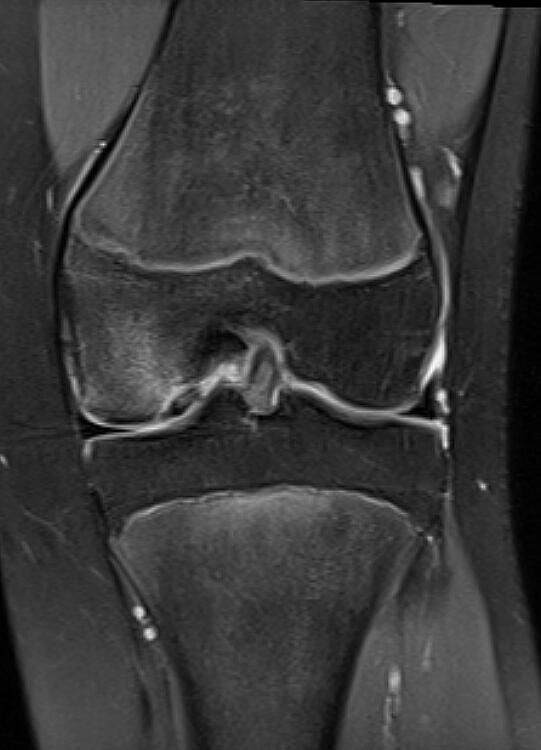

Patellar tendinopathy (MRI scan)

Adolescent osteochondral injury (MRI)